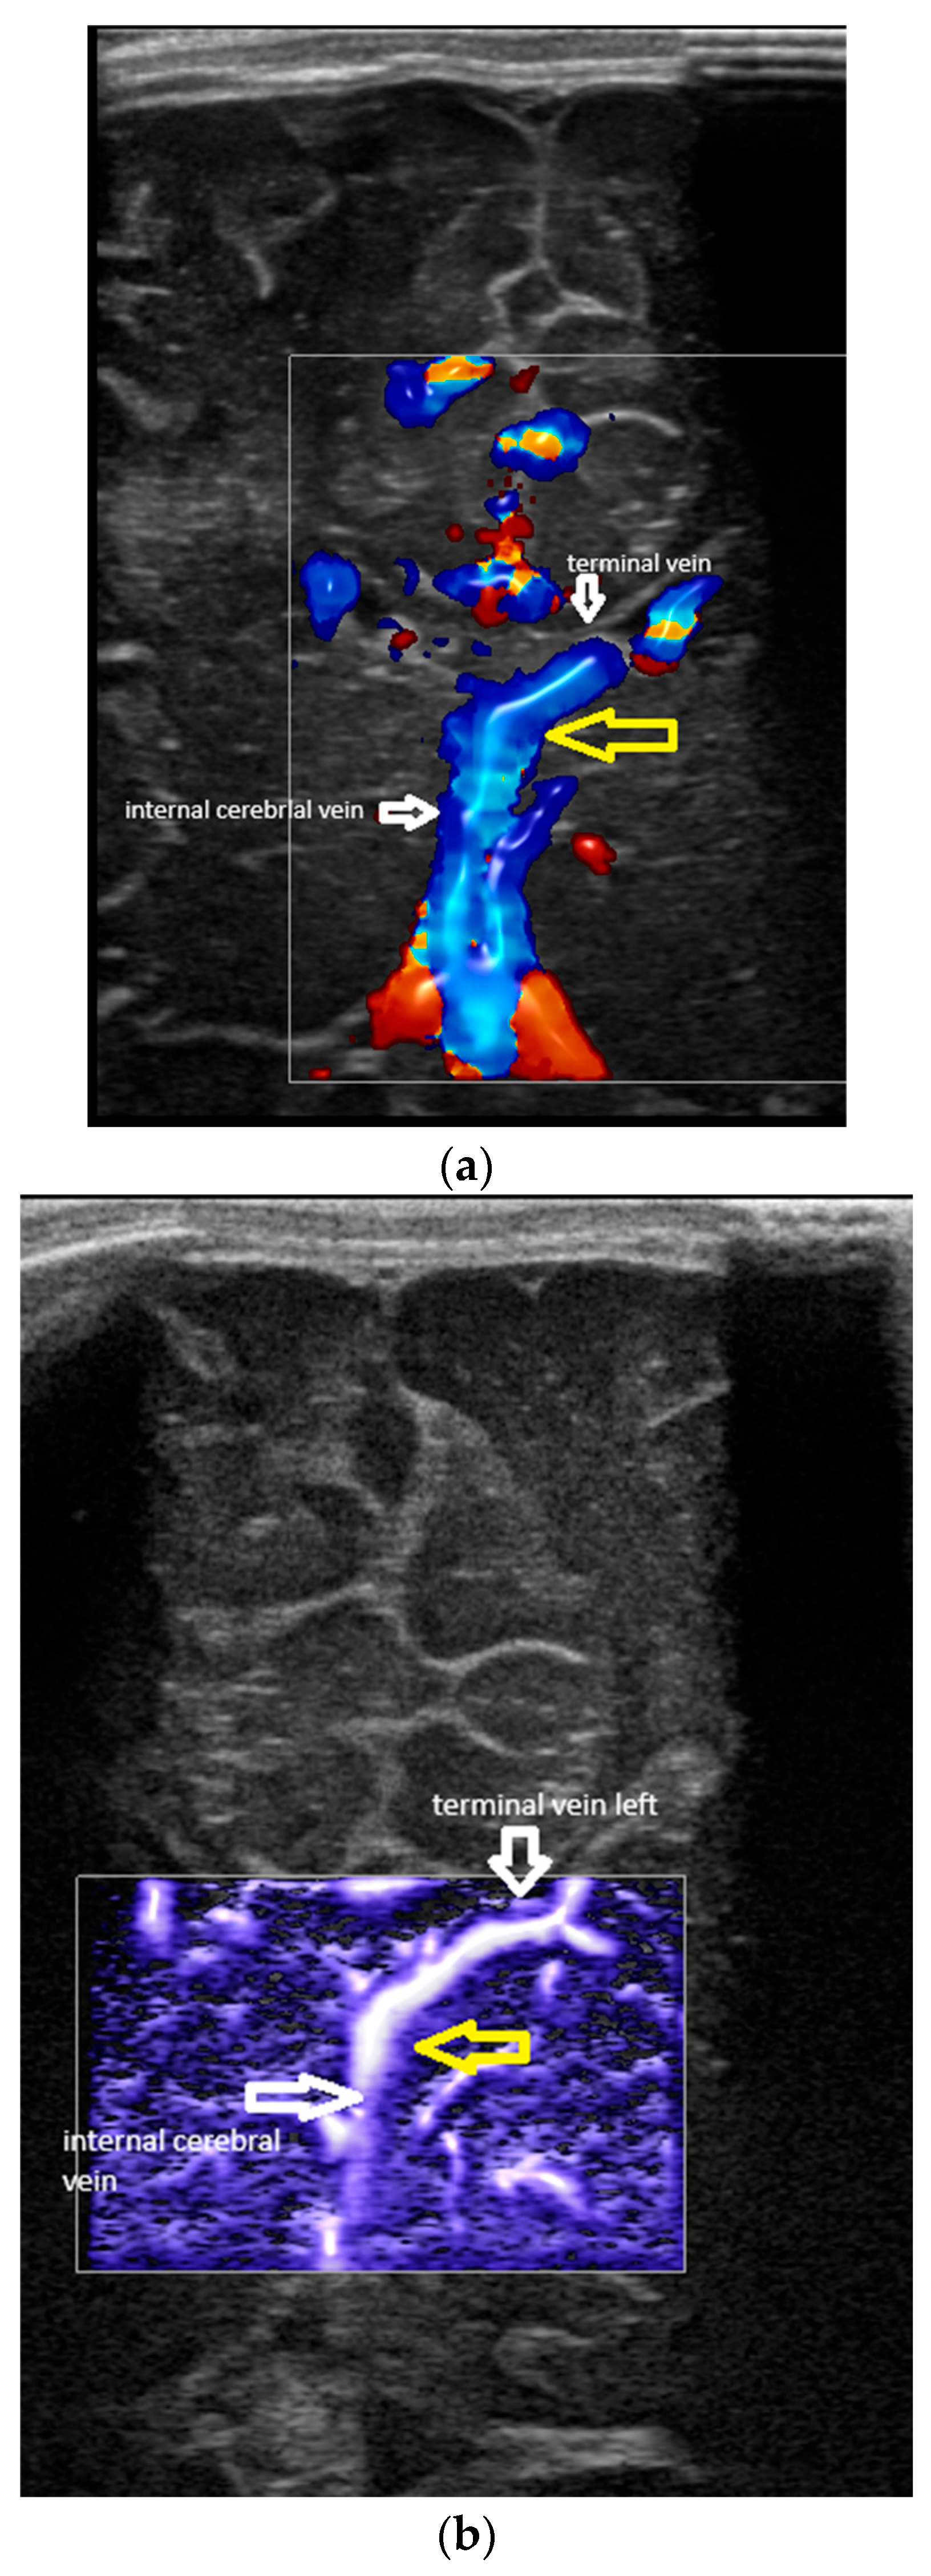

- Confluence posterior to the foramen of Monro, the most frequent variant (Figure 1).

- Confluence at the level of the foramen of Monro (Figure 2).